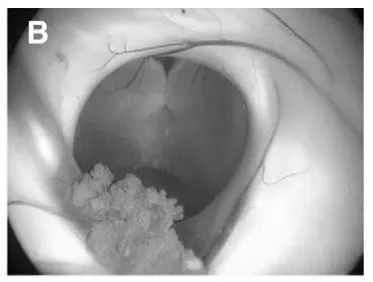

对于因中脑导水管受压而导致梗阻性脑积水的肿瘤,最根本的脑脊液循环恢复策略仍是肿瘤全切除,可惜多数瘤体过大,难以单纯经内镜彻底切除。采用先进行神经内镜第三脑室造瘘(B–F内镜下视野),然后再开颅切除肿瘤,过程如下。

(B)室间孔(Monro孔),选取可同时抵达第三脑室底及肿瘤之入路。